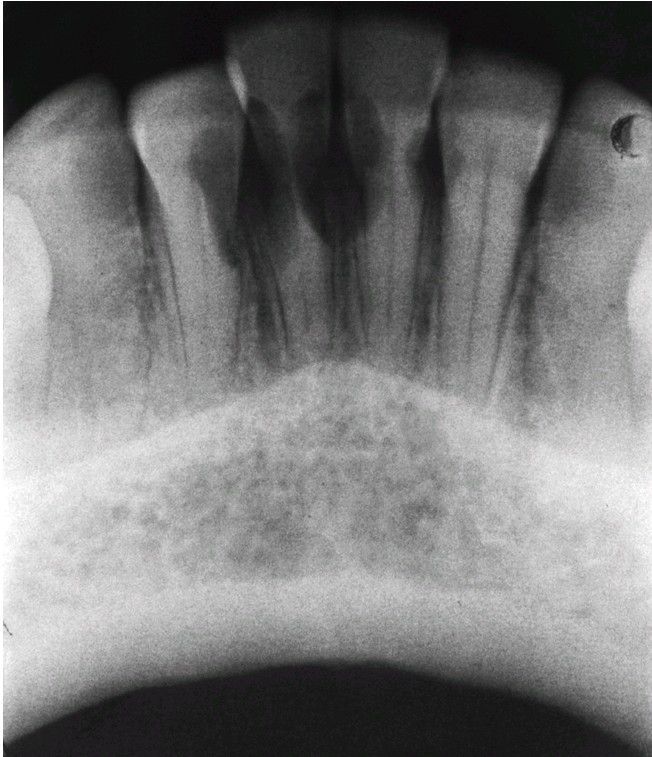

Multiple Idiopathic Root Resorption.

Extensive invasive cervical resorption of several anterior mandibular teeth.